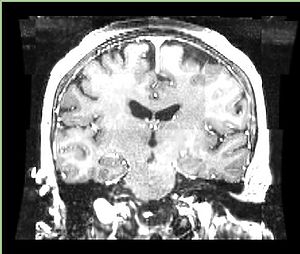

• Input images: isotropic post-contrast T1 MRI acquired at different locations of BWH during 2006-2008, used under medical records study IRB. Time period between acquisition of scans for each patient is about 1 year.

• images were acquired with the same sequence, but possible on different scanners, all scans are axial